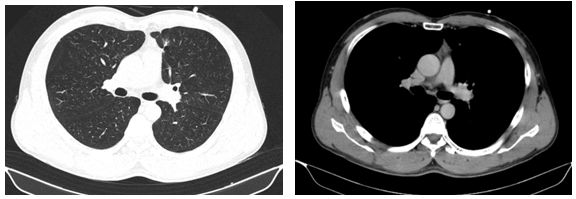

-         MRI sọ não:

Hình 4. Trên phim chụp MRI sọ não: Rải rác trong nhu mô trên và dưới lều có các nốt ngấm thuốc, lớn nhất vị trí cạnh não thất bên bên phải đường kính ~11mm – Theo dõi tổn thương thứ phát

Cộng hưởng từ sọ não:

Sau 6 tháng điều trị: Nhu mô não vùng trên và dưới lều tiểu não: hình dạng và cấu trúc bình thường, tín hiệu đồng nhất, ranh giới chất trắng và chất xám rõ. Không thấy tổn thương khu trú hoặc lan tỏa.